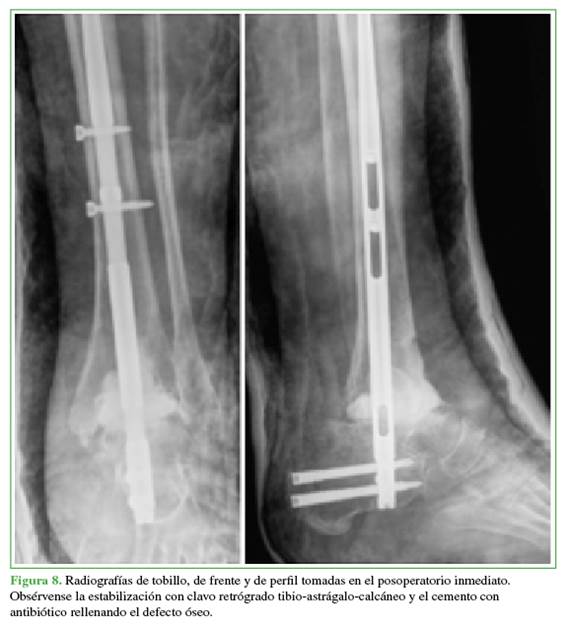

En la primera cirugía, se efectuó un abordaje anterior de tobillo ampliado sobre la cicatriz quirúrgica. Se retiraron los componentes de la prótesis, se tomaron muestras de hueso remanente para estudio bacteriológico y se desbridó hasta obtener hueso vital y sangrante. Se constató un defecto óseo remanente de 2,5 cm. Se procedió a la distracción para mantener la longitud del miembro y se colocó, de forma retrógrada, un clavo tibio-astrágalo-calcáneo. El defecto óseo se rellenó con dos dosis de cemento con 2 g de vancomicina por dosis (Figura 8).